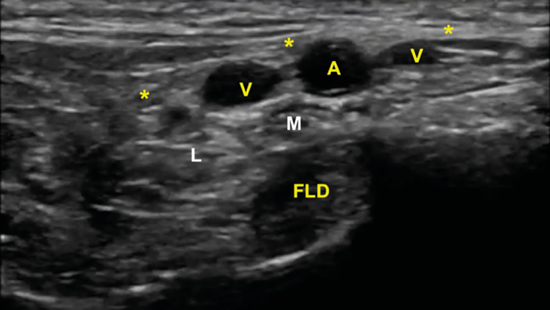

El nervio tibial, que se sitúa en superficie a las estructuras musculotendinosas y bajo la fascia crural, de forma habitual está dispuesto posterior a los vasos tibiales posteriores (Figura 6).

Figura 6. Túnel tibiocalcáneo. El examen en eje corto, bajo la fascia crural (*) y de anterior a posterior, muestra el tendón tibial posterior (TP), el tendón flexor largo de los dedos (FCD) aún con fibras musculares, y el músculo flexor largo del primer dedo (FLD). Entre estas dos estructuras se encuentra el haz neurovascular que está formado por las venas (V), la arteria (A) tibial posterior y por el nervio tibial (rodeado por X).

El nervio tibial tiene forma más o menos redondeada, patrón fibrilar con zonas punteadas anecogénicas e hiperecogénicas que corresponden a los haces nerviosos y al tejido conectivo de sostén, la típica imagen denominada de “sal y pimienta”, y sección transversal entre 10 mm26 y 12,7 mm27 a nivel del maléolo tibial (Figura 7).